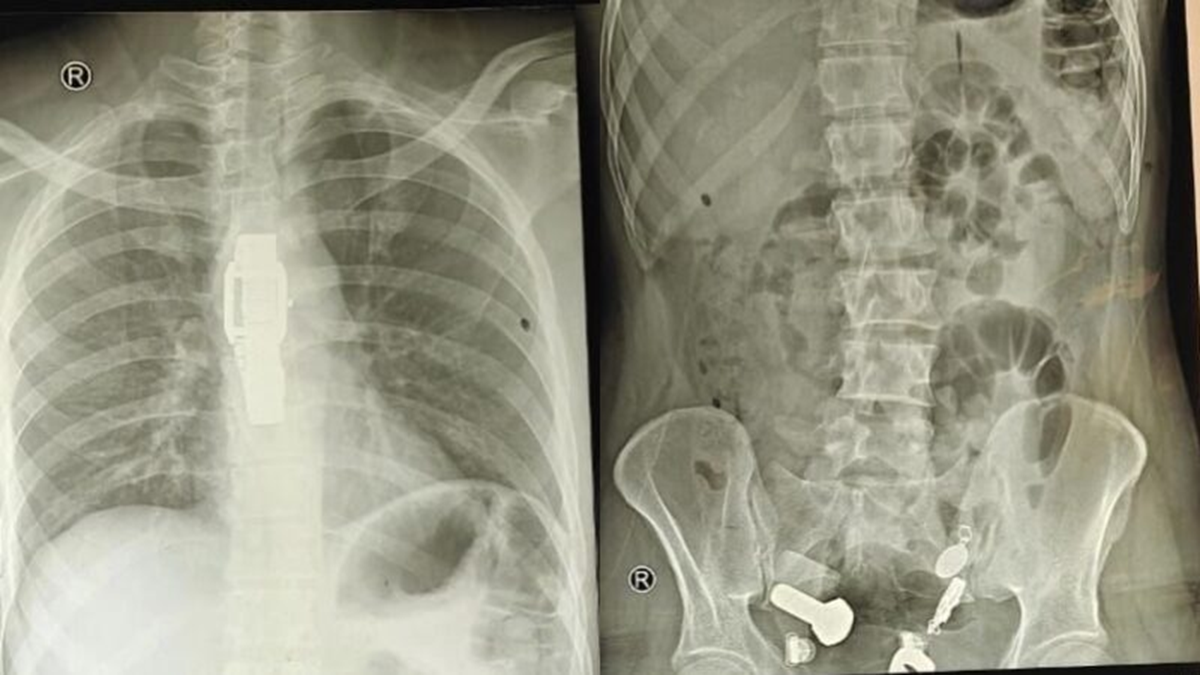

Một người đàn ông ở Ấn Độ gần đây đã nhập viện vì đau dạ dày dữ dội, khiến anh ta khó ăn. Ban đầu, các bác sĩ nghi ngờ đây chỉ là một vấn đề tiêu hóa đơn giản, nhưng kết quả chụp X-quang cho thấy một vật thể lạ bên trong cơ thể anh ta.

Các bác sĩ đã vô cùng kinh ngạc khi phát hiện một chiếc đồng hồ và vô số ốc vít trong bụng anh ta. Ca phẫu thuật kéo dài ba giờ.

Sau khi thăm khám và chụp X-quang, các bác sĩ thấy một chiếc đồng hồ đeo tay, bu lông và ốc vít, được gắn chặt vào nhau... trong bụng bệnh nhân.

Các bác sĩ đã cố gắng sử dụng ống nội soi để lấy vật thể ra nhưng không thành công, sau đó phải tiến hành một cuộc phẫu thuật lớn kéo dài hơn ba giờ để lấy toàn bộ dị vật ra khỏi cơ thể.